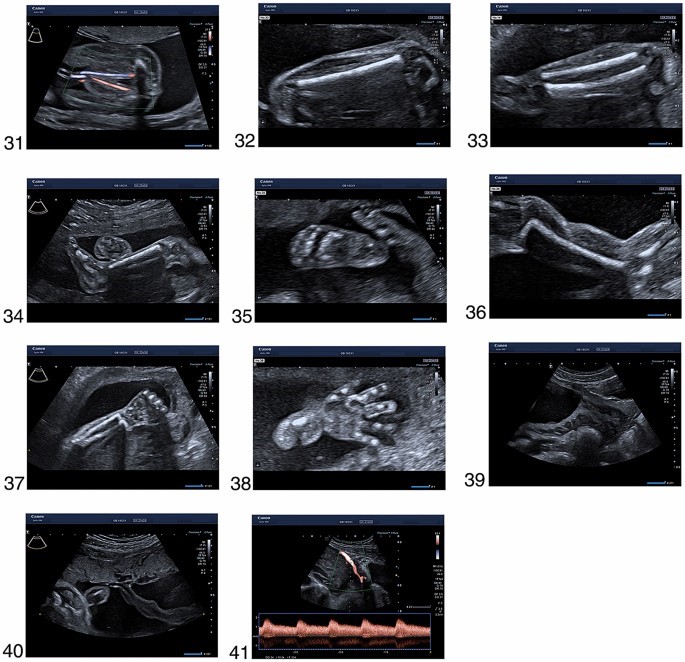

مجموعه تصاویر محصور شده در شرایط ایده آل در بیماران با شاخص توده بدنی پایین، جنین در وضعیت مطلوب، مایع آمنیوتیک طبیعی، بدون فیبروم و بدون ناهنجاری رحمی به دست آمد. آنها همچنین در یک سری از بیماران به دست می آیند. بنابراین، ما اذعان داریم که در عمل بالینی روزمره، ممکن است با موقعیتهایی مواجه شویم که در آن به دست آوردن تصاویر با چنین کیفیتی امکانپذیر نباشد. با این حال، هر تلاشی باید برای نشان دادن تمام ساختارهای مربوطه انجام شود. اگر این امکان وجود ندارد، ممکن است لازم باشد جنین را به آرامی با دست دیگر حرکت دهید، از بیمار بخواهید به پهلو بچرخد، بیمار را به پیاده روی بفرستد و مثانه را خالی کند یا در نهایت بیمار را برای 2 هفته مجدد رزرو کنید. بعدا برای یک معاینه سونوگرافی دقیق دیگر. هر محدودیتی که بر کیفیت تصویر تأثیر می گذارد باید در گزارش ذکر شود .

- استخوان ران

- نمای جلویی ساق پا با استخوان درشت نی و پرونئوس

- ساق با درشت نی و زاویه صحیح مفصل تالوکرال

- پا (*، + ،#)، 36. شانه و بازو

- ساعد با شعاع و اولنا

- دست

39 نمای ترانس شکمی دهانه رحم

- جاگذاری جفت بند ناف

- شریان رحمی